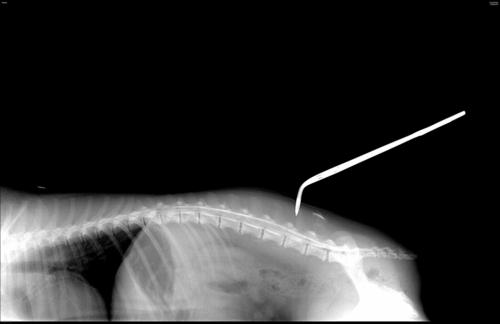

Инъецирование контрастного вещества в субарахноидальное пространство осуществляют двумя доступами: окципитальным (в области шейного отдела позвоночного столба между затылочной костью и первым шейным позвонком) или люмбальным (в области поясничного отдела позвоночного столба). Выбор в каждом конкретном случае индивидуален и зависит от многих факторов.

Рентгенографические снимки сначала выполняют без введения контрастного вещества в 2-х взаимно перпендикулярных проекциях. После введения контрастирующего вещества выполняют серию рентгенологических снимков через определенные промежутки времени в 2-х а иногда и в 3-х проекциях (правая латеральная, вентро-дорсальная, косая проекция) для лучшей визуализации и латерализации поражения.

Просматривая и интерпретируя изображение, полученное в результате проведения контрастного исследования спинного мозга, ветеринарный специалист оценивает прохождение контрастного вещества по субарахноидальному пространству, сравнивает изображение с нормой и отвечает на вопрос в каком отделе позвоночного столба произошла компрессия спинного мозга.